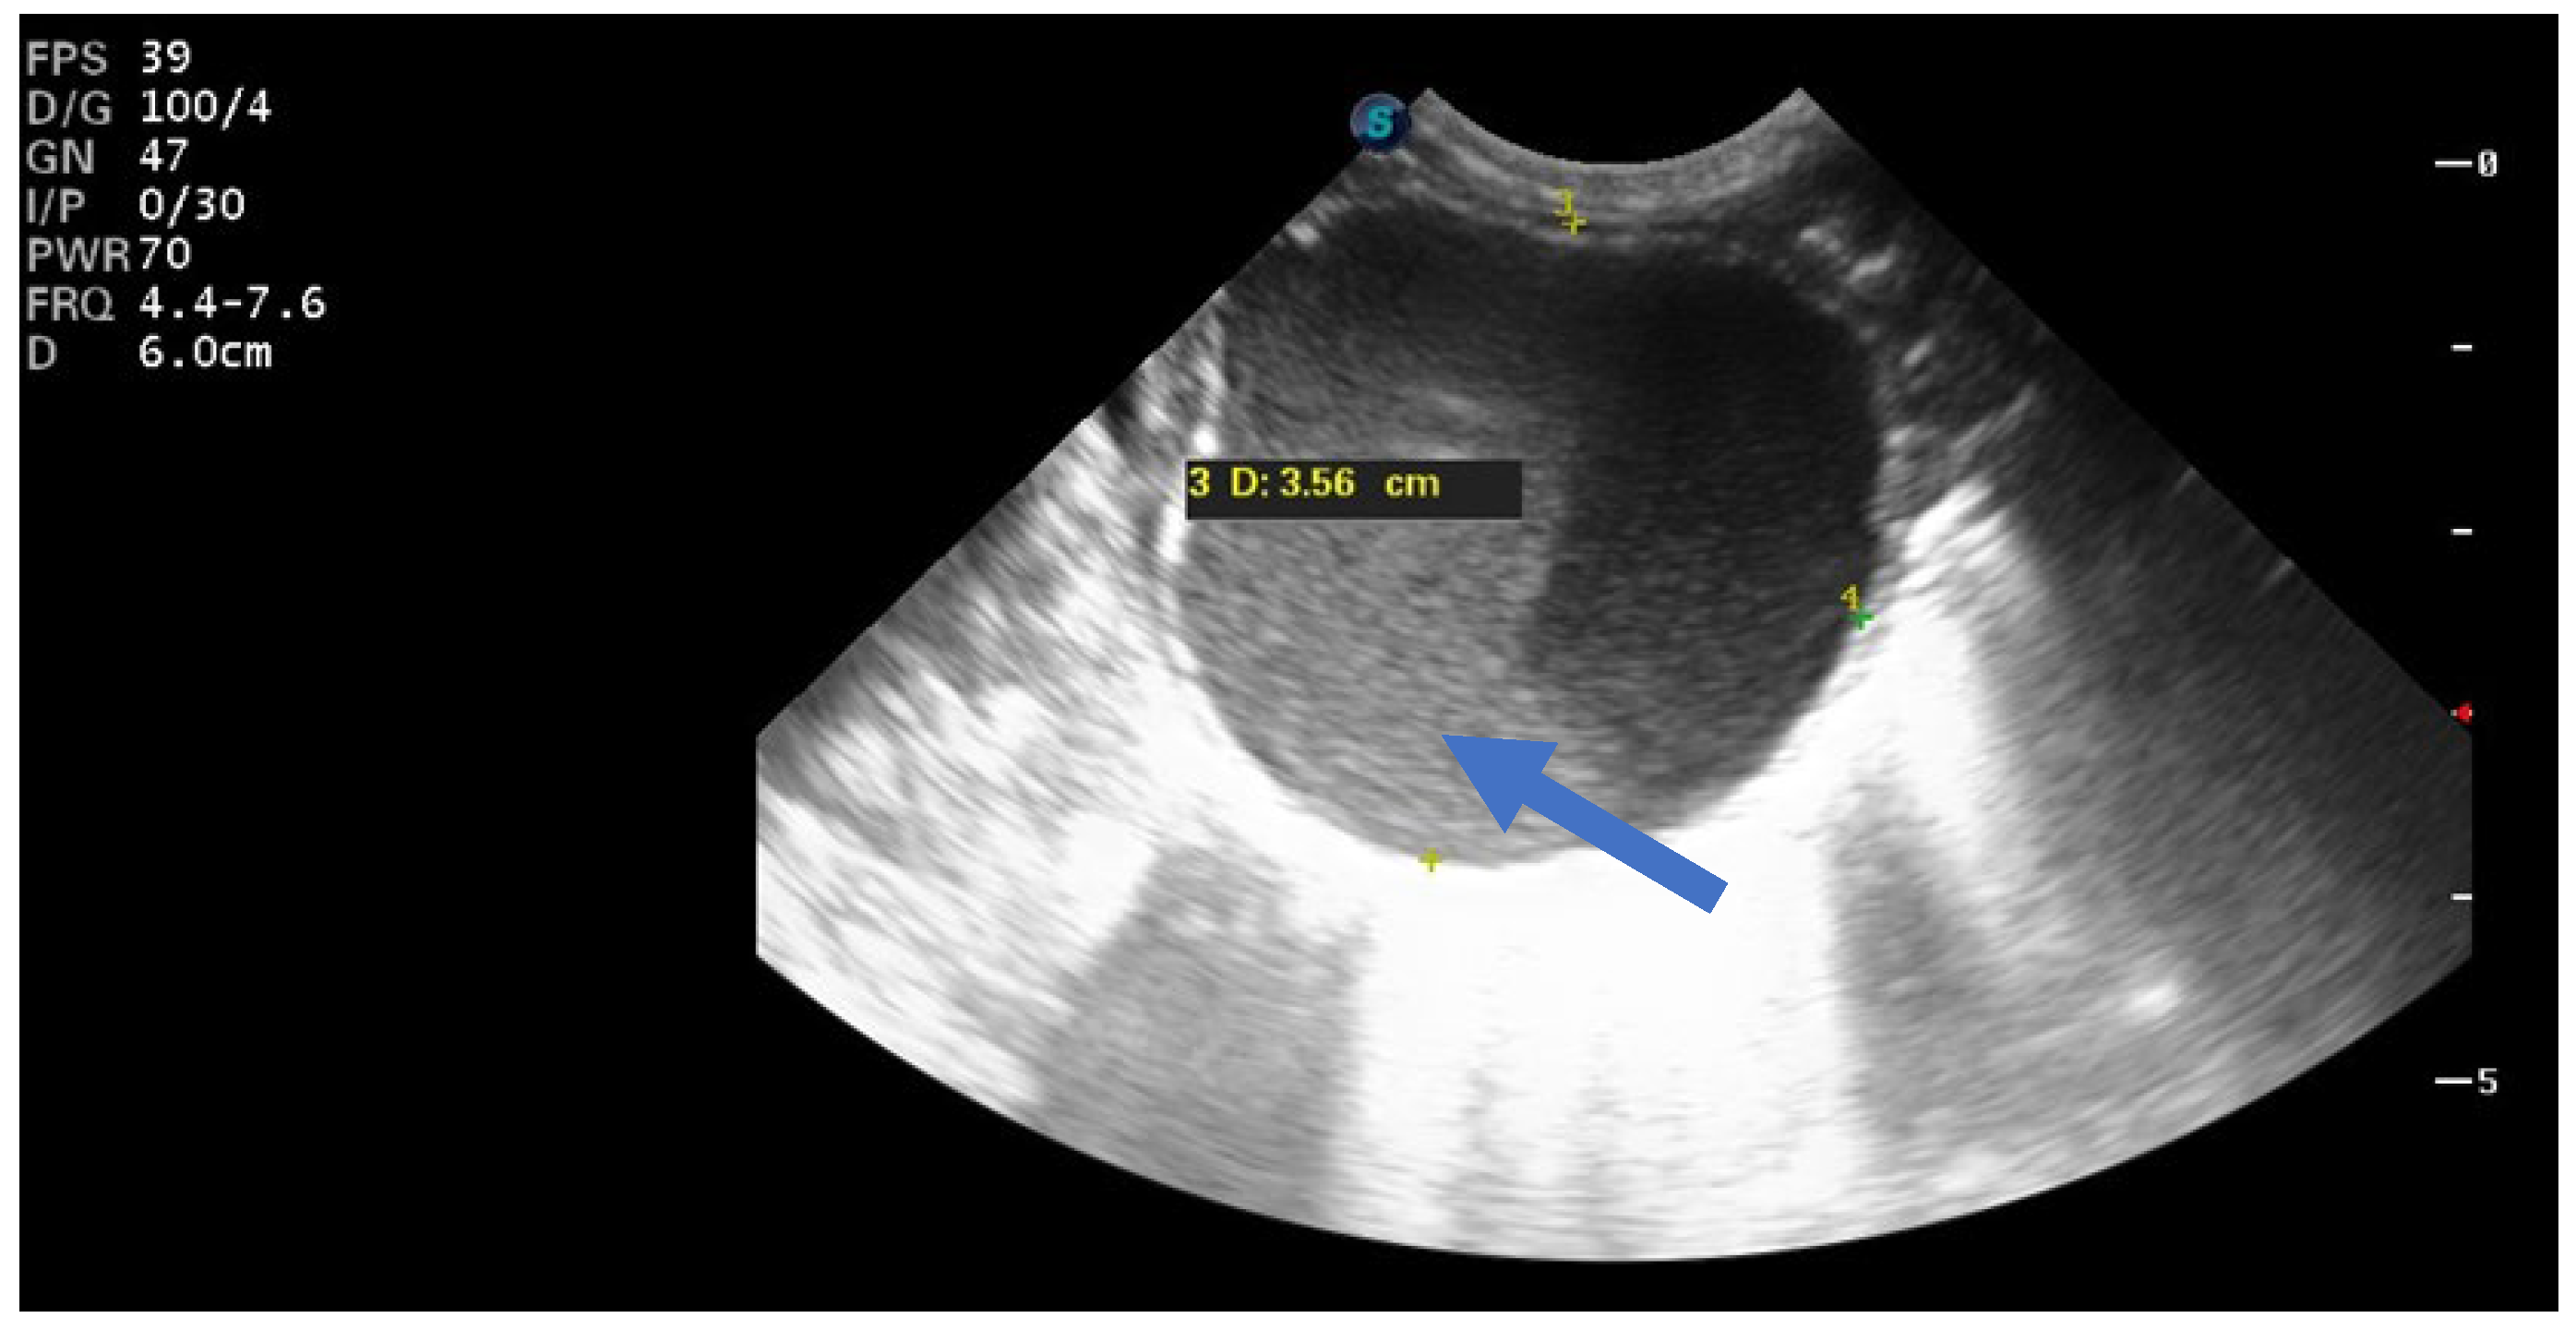

Of the nine simple cysts, seven regressed spontaneously within the first two months after birth (Figure 5 and Figure 6).

Figure 5.

Ultrasound image of a simple cyst with an intracystic blood clot (arrow) at the age of 2 weeks postpartum, which regressed spontaneously at 2 months.